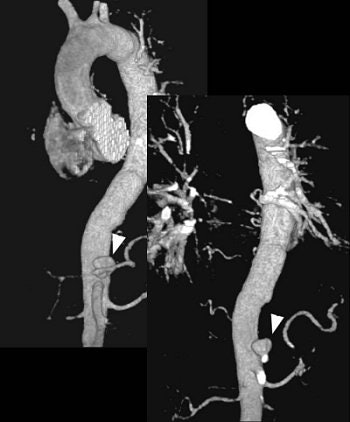

Aortic dissection assessment, before (above) and after (below) surgery.